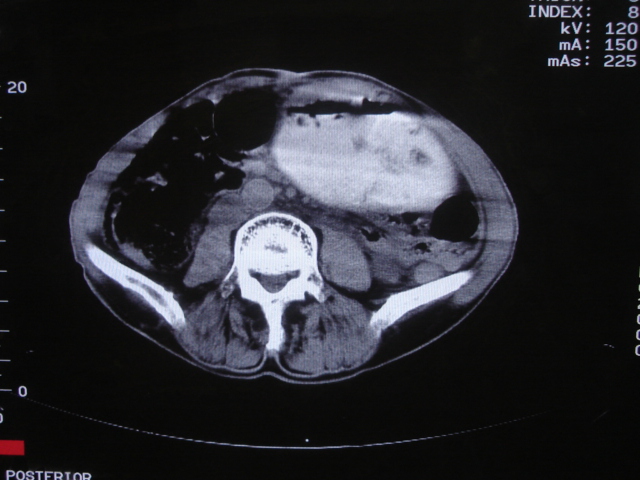

以下是引用深泽交通医院在2008-7-17 12:39:00的发言:[br]胃下垂;胃窦占位

以下是引用杀毒软件在2008-7-17 16:45:00的发言:[br][br] 建议胃镱检查!考虑胃窦部占位